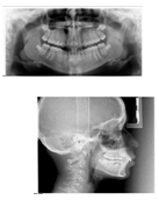

多彩な機能が搭載されたドイツ・カボ社製の歯科用CT装置を導入しました。

撮影時間はわずか10秒程度。患者さんの被ばくを最小限に抑えることが出来ますので、インプラント治療でも安心して検査を受けていただけます。

従来ではわかりにくかった詳細な歯の構造が立体的(3D)に把握でき、高解像度撮影が可能で極めてシャープな画像化が可能で従来より確実性の高い診断が可能となります。

例えば智歯(親知らず)の抜歯やインプラントの埋入手術などは周囲の神経との位置関係が明瞭にわかり、安全性がより高まります。